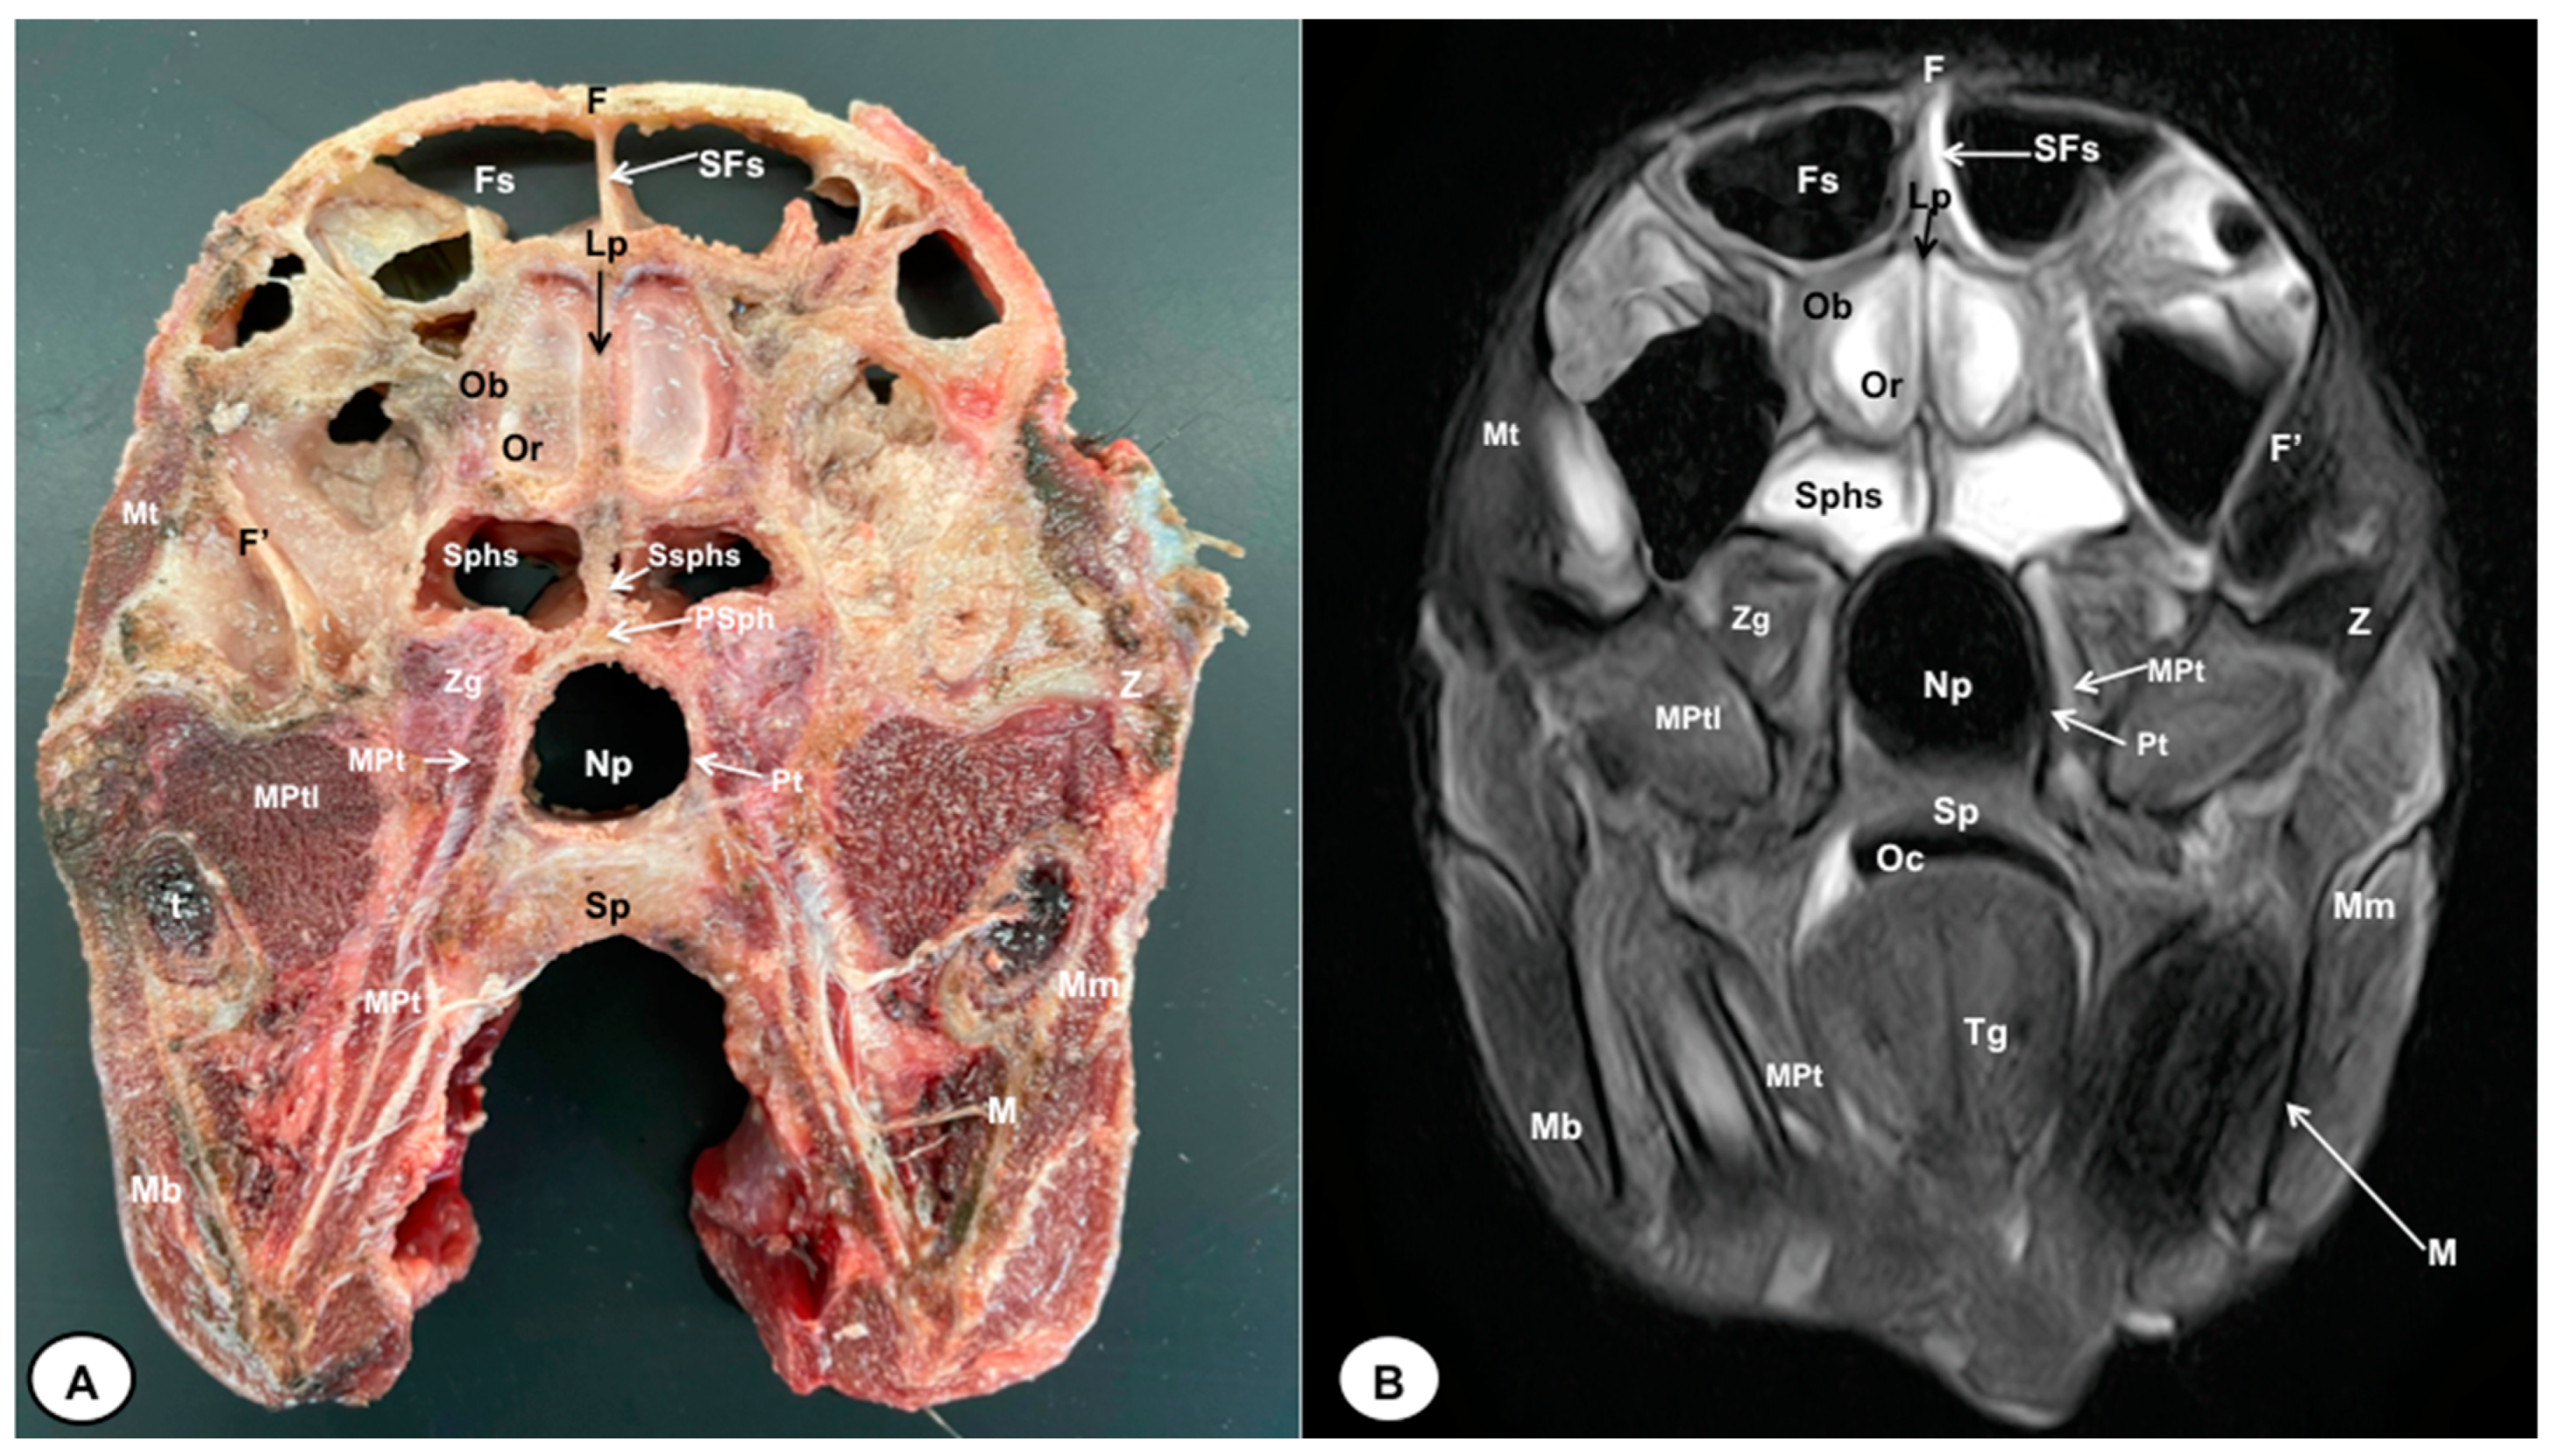

Figure 3.

Transverse cross-section (A) and T2W MR (B) images of the crested porcupine head at the level of the olfactory bulb corresponding to line II in Figure 1. F: frontal bone; F′: orbital plate of frontal bone; Fs: frontal sinuses; SFs: septum of frontal sinuses; Ob: olfactory bulb; Or: olfactory recess; Lp: Lamina perpendicularis ossis ethmoidei; Sphs: sphenoid sinus; Ssphs: septum of sphenoidal sinuses; PSph: presphenoid bone; Np: nasopharynx; Pt: pterygoid bone; Sp: soft palate; Oc: oral cavity; MPt: Musculus pterygoideus medialis; MPtl: Musculus pterygoideus lateralis; Mt: Musculus temporalis; Zg: zygomatic glands; Z: zygomatic bone; t: tooth; M: mandible; Mm: Musculus masseter; Mb: Musculus buccinator; Tg: tongue.

The anatomical sections obtained in this study allowed us to visualize the different structures belonging to the central nervous system and its associated structures, which were labeled according to the International Committee on Veterinary Gross Anatomical Nomenclature. Therefore, we identified the main components of the brain (the prosencephalon, mesencephalon, and rhombencephalon). Thus, the two telencephalic hemispheres surrounded by the cerebral cortex and separated by the longitudinal cerebral fissure were identified (Figure 5A, Figure 6A and Figure 7A). Both hemispheres were connected by fibers of white matter known as the corpus callosum (Figure 4A, Figure 5A, Figure 6A and Figure 7A). Each cerebral hemisphere contained a lateral ventricle (Figure 4A, Figure 5A, Figure 6A and Figure 7A). Ventrally, we distinguished a component of the basal ganglia, the nucleus caudatus (Figure 4A and Figure 5A). Thus, we identified different parts of it, such as the head and the tail. Other structures which we observed were the septal nuclei, which were circumscribed by two parallel vertical lines through the most inferior and medial aspect of each lateral ventricle (Figure 4A). More caudally, the diencephalon enclosing the third ventricle was identified, as well as more ventrally specific components of the hypothalamus, such as the optic chiasm (Figure 4A and Figure 5A). Additionally, these sections were quite helpful in showing the caudal parts of the thalamus. Hence, the lateral eminence on the caudodorsal surface of the thalamus, known as the lateral geniculate body, was distinguished, whereas caudoventrally, we identified the medial geniculate body of the thalamus (Figure 5A). Moreover, the dorsal part of the mesencephalon with the caudal and rostral colliculus and its ventral part with the cerebral peduncles were also shown (Figure 6A and Figure 7A). These anatomical sections were helpful in identifying the vermis and the cerebellar peduncles, which connected the cerebellum to the adjacent brain stem and the cerebrum (Figure 7A). The ventral part of the cerebellum with the lingula, covering part of the fourth ventricle, could also be identified (Figure 7A). These sections were also helpful in distinguishing the medulla oblongata and the decussation of the pyramids. In addition, different bony structures comprising the neurocranium were observed, such as the frontal, the temporal (with its scamous, petrous, and tympanic parts), the sphenoid, and the occipital bones (Figure 2A, Figure 3A, Figure 4A, Figure 5A, Figure 6A and Figure 7A). Furthermore, these sections showed different air-filled spaces, such as the frontal and the sphenoidal sinuses (Figure 2A, Figure 3A, Figure 4A, Figure 5A, Figure 6A and Figure 7A), and structures associated with the nasal cavity, including the ethmoturbinates and the vomer, could be distinguished (Figure 2A and Figure 3A). Main sensory organs such as the eyeball and its associated structures were also depicted. Consequently, we identified the retina, the vitreous chamber, and the optic nerve, which were surrounded by extraocular muscles. Among these, we distinguished the dorsal and ventral rectus muscles (Figure 2A). Moreover, the main components of the auditory system, such as the external auditory canal, the tympanic cavity, and the inner ear, were visualized (Figure 5A and Figure 6A). Also, we identified the relevant muscles related to masticatory function, such as the temporalis, the medial and lateral pterygoid muscles, the masseter, the digastric muscle, and other important muscles, including the buccinator muscle and the longissimus capitis of the head (Figure 2A, Figure 3A, Figure 4A, Figure 5A, Figure 6A and Figure 7A).

No significant anatomic differences were identified subjectively in the three porcupines which were imaged. Most anatomic structures distinguished on T2-weighted images of the cadaver specimens matched adequately with structures identified in the corresponding anatomical cross-sections. Hence, the central nervous system structures of the porcupine head, the eyeball’s structures (vitreous humour and lens), and the masticatory muscles showed an accurate visualization using T2W MR images. Nonetheless, the bones that comprised the neurocranium, such as the frontal, the parietal, the temporal, the occipital, and the sphenoid bones, were identified with a hypointense signal (Figure 2B, Figure 3B, Figure 4B, Figure 5B, Figure 6B, Figure 7B, Figure 8 and Figure 9).